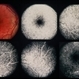

- Fundus Albipunctatus

- Fundus albi